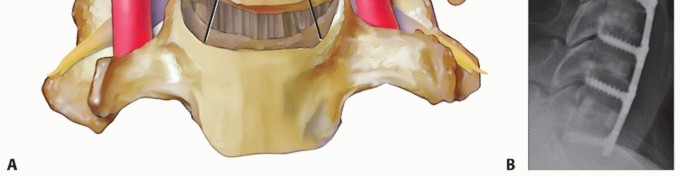

### TECH FIG 6 • Commercially available sizers are used to determine optimal graft size. A trial that fits snugly under gentle Caspar distraction will suffice. If autograft is used, the appropriate trial is used as a template for cutting the autograft bone. The surgeon should try to place a graft that fills the space as much as possible without overdistracting, which can cause posterior neck pain, or entering the spinal canal. We generally prefer to use commercially prepared cortical allografts for ACDF, except in patients with poor healing potential. Alternatively, autograft iliac crest bone can be used. ### Determining Plate Length Plating is optional for one-level ACDF with autograft. If allograft or multilevel surgery is performed, plating is recommended. Once the graft has been placed, the size of the plate is then determined. Optimal plate length is one that allows for the screws to be immediately adjacent to the endplates (TECH FIG 7). This plate length allows for screws that angle away from the disc space, which in turn allows for screws that are longer than ones directed parallel to the disc space, yet are short enough to avoid entry into the supra- and infraadjacent disc spaces. This length also prevents impingement of the plate into the adjacent disc spaces. ### Plating Techniques The plate should be contoured into lordosis to lie flush against the vertebral bodies. It should also be centered coronally within the margins of the uncinate processes. Screws should also be angled medially to decrease the chance of lateral injury to nerve roots or vertebral arteries.

### TECH FIG 7 • Proper plate sizing. A. The length of an optimally sized plate is such that the screw holes at the top and bottom of the construct are immediately adjacent to their respective endplates. In this example, even though this was done, the plate is still closer to the cephalad adjacent disc space than ideal because the vertebral bodies in this patient are relatively short. Nevertheless, adjacent-level disc degeneration did not occur in this patient at 2-year follow-up. Bicortical screw purchase is not routinely needed, but estimates of screw length can be obtained by measuring MRI or CT scans preoperatively. Screws should be angled away from the disc space to provide greater length and divergent fixation, which may better resist pullout. B. In another patient with short vertebrae who presented to us with adjacent level disease, the plate was placed too close to the adjacent disc, resulting in adjacent-level ossification disease (arrow). The cephalad screws are not immediately adjacent to the endplate but rather inserted at roughly the midpoint of the vertebral body. Similarly, the caudal screws begin in the midportion of the vertebral body. The plate is too long distally and comes close to the subjacent disc as well. As demonstrated by these examples, proper plate sizing is especially important in patients with shorter vertebrae where the adjacent discs are closer together. C. Screw fixation and graft carpentry. This patient underwent C6-C7 ACDF for cervical myeloradiculopathy. Because he had a very wide and deep disc space, two bone grafts were inserted side by side and rotated 90 degrees to the usual orientation in order to better fill the disc space, increase contact through the fusion area, and improve load sharing across the construct. Screw lengths were also optimized to improve fixation. The screw length can be estimated preoperatively by measuring the depth of the vertebral body on CT or MRI scans. Ideally, screws are as long as possible within the vertebral body to maximize fixation. Dynamic plates can be used if desired (TECH FIG 8). They have the theoretical benefit of improving load sharing on the graft. There are several types of dynamic plates. Variable screw systems allow for toggling within a fixed screw hole with settling of the construct. A potential downside is that the screw can loosen within bone as toggling occurs. Slotted plates have holes that allow screws to translate longitudinally as the construct shortens. The screws are rigidly fixed to bone and do not toggle, but excessive translation may lead to adjacent-level plate impingement. Telescoping plates use fixed screws in nonslotted holes but the ends of the plate telescope with respect to each other as settling occurs. Postoperative adjacent-level plate impingement will not occur with this design if the plate is properly positioned at the time of surgery, as the distance from the end of the plate to the endplate does not change with construct shortening. However, these plates tend to be somewhat thicker. If dynamic plates are used, the surgeon must perform the plating procedure to accommodate the anticipated settling without overlapping uninvolved adjacent discs.8 In general, we prefer rigid plating in most cases to avoid excessive construct settling. Variable plating has not been clearly demonstrated to improve outcomes or fusion rates. 8